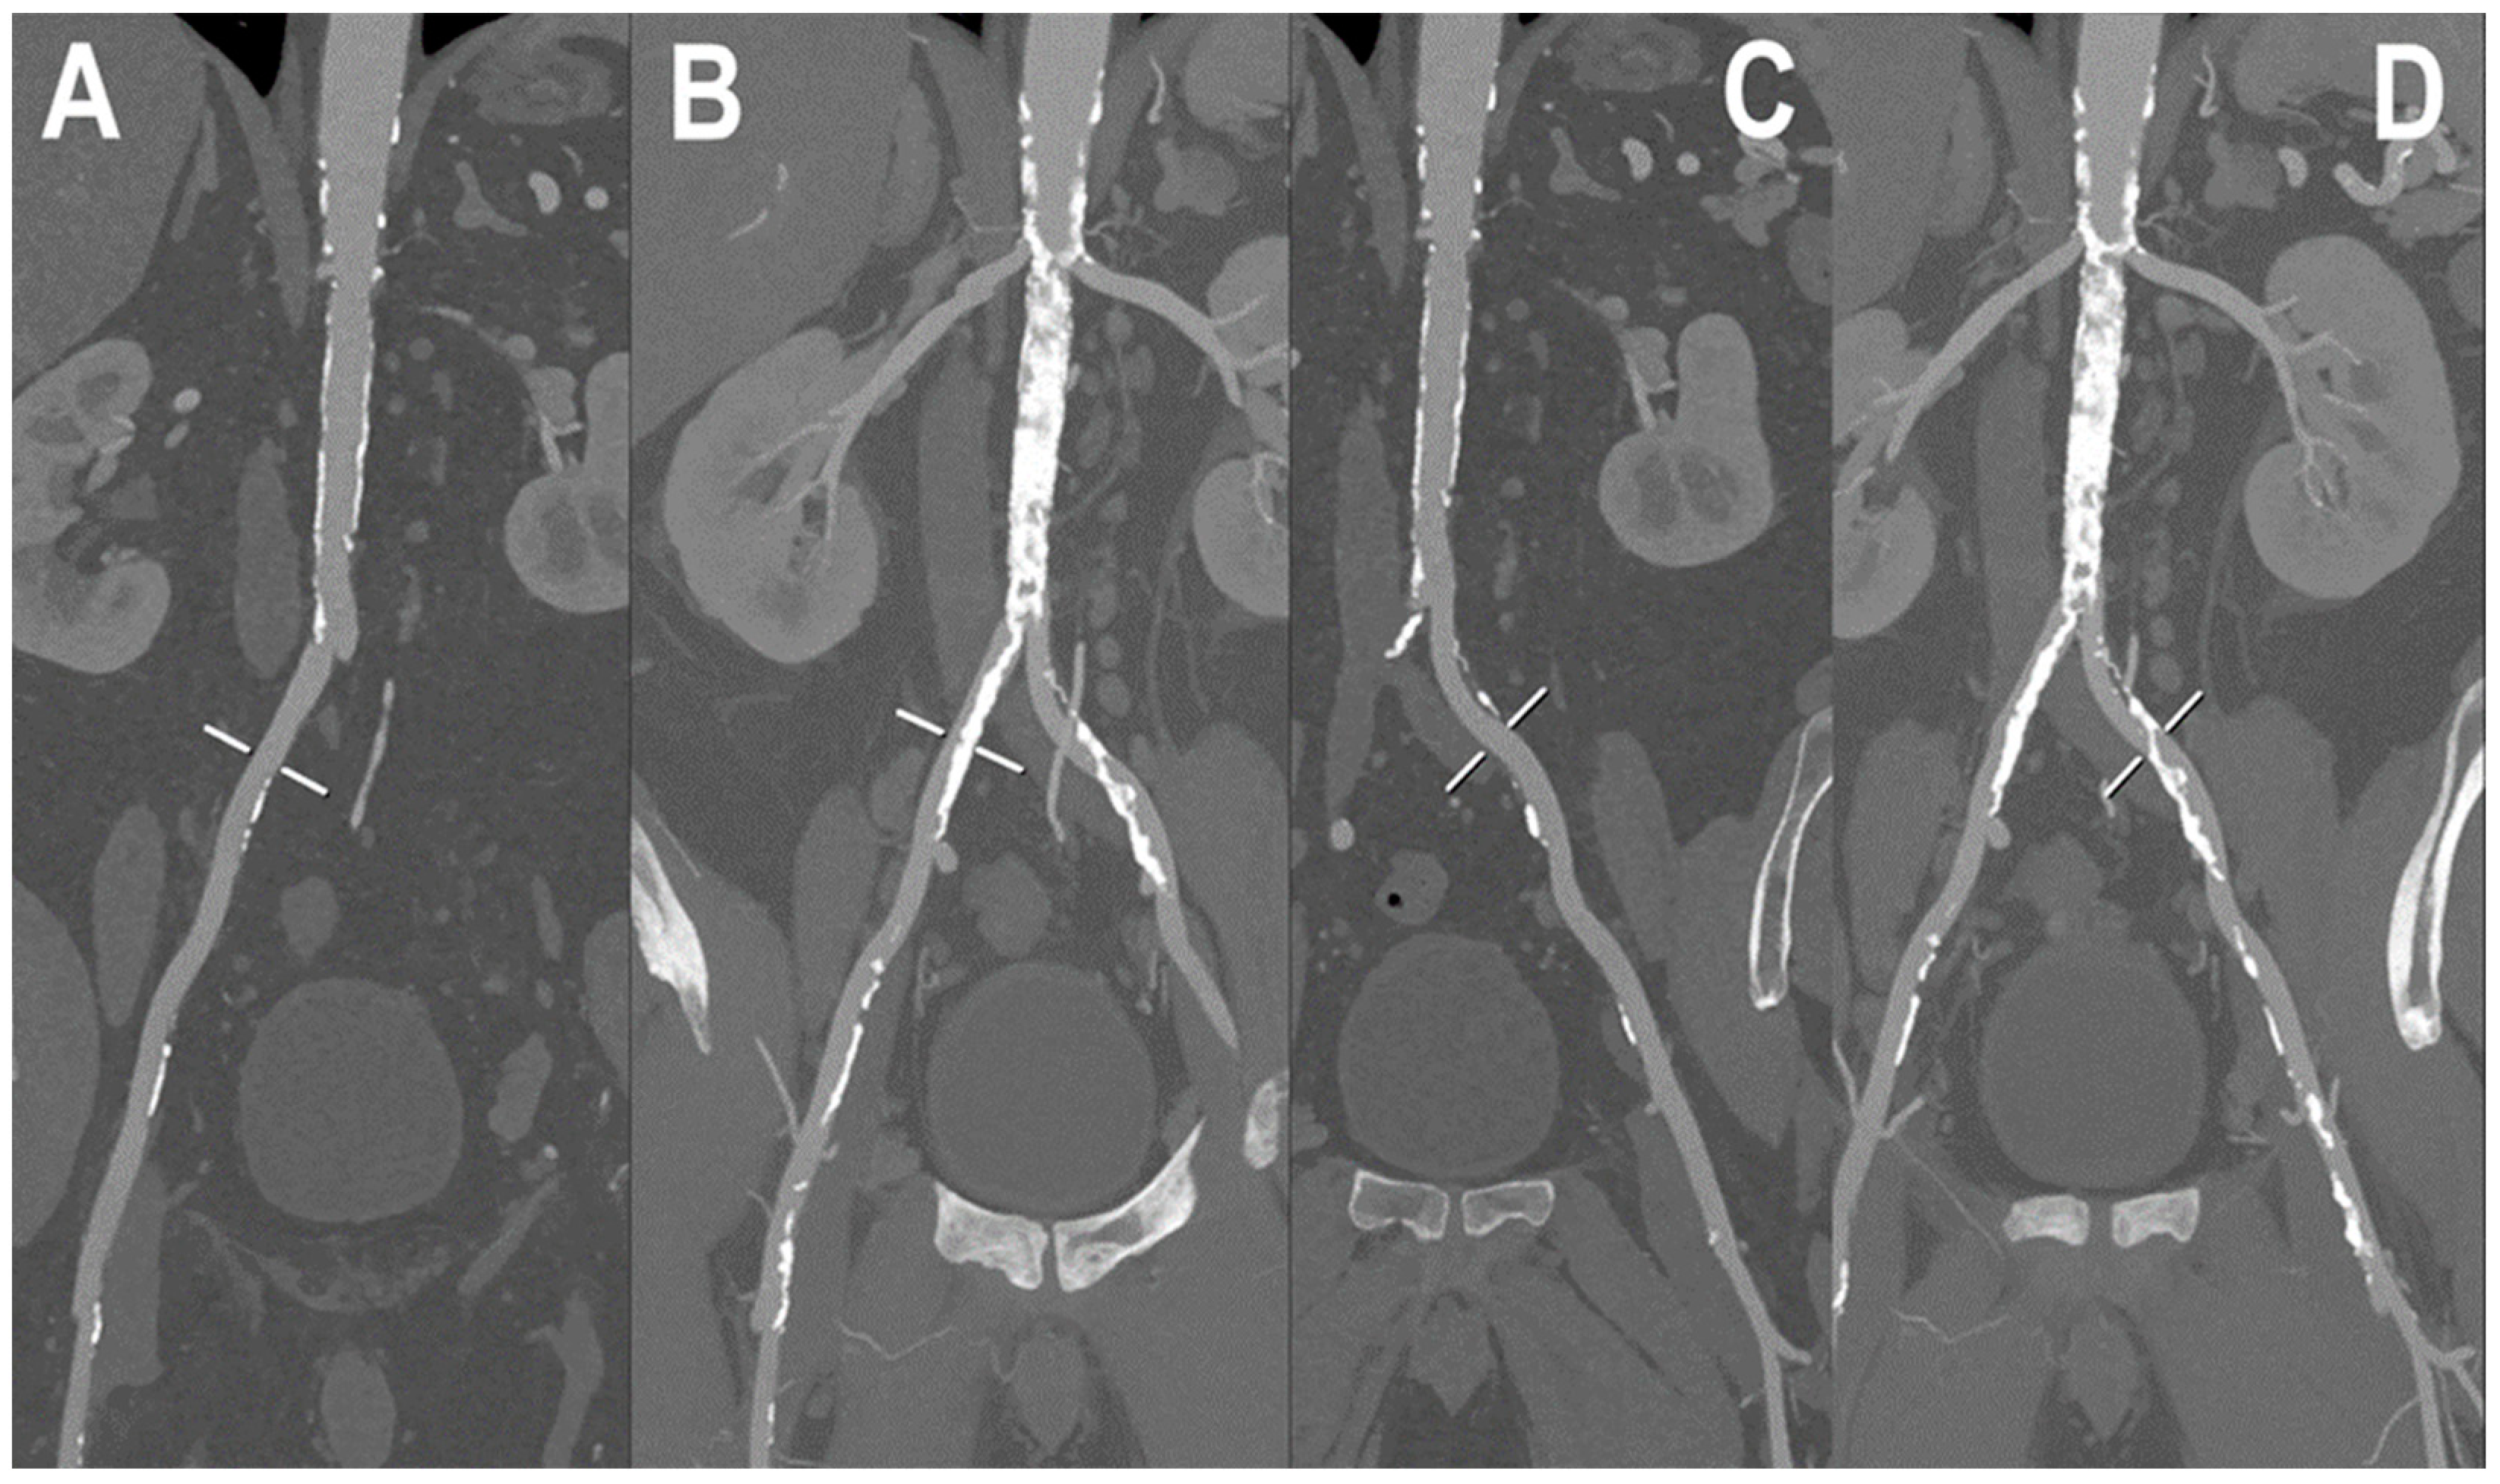

- Shwaiki, O.; Rashwan, B.; Fink, M.A.; Kirksey, L.; Gadani, S.; Karuppasamy, K.; Melzig, C.; Thompson, D.; D’Amico, G.; Rengier, F.; et al. Lower extremity CT angiography in peripheral arterial disease: From the established approach to evolving technical developments. Int. J. Cardiovasc. Imaging 2021, 37, 3101–3114. [Google Scholar] [CrossRef] [PubMed]

- Meyer, B.C.; Werncke, T.; Foert, E.; Kruschewski, M.; Hopfenmüller, W.; Ribbe, C.; Wolf, K.J.; Albrecht, T. Do the cardiovascular risk profile and the degree of arterial wall calcification influence the performance of MDCT angiography of lower extremity arteries? Eur. Radiol. 2010, 20, 497–505. [Google Scholar] [CrossRef]

- Li, Z.; Leng, S.; Halaweish, A.F.; Yu, Z.; Yu, L.; Ritman, E.L.; McCollough, C.H. Overcoming calcium blooming and improving the quantification accuracy of percent area luminal stenosis by material decomposition of multi-energy computed tomography datasets. J. Med. Imaging 2020, 7, 053501. [Google Scholar] [CrossRef] [PubMed]